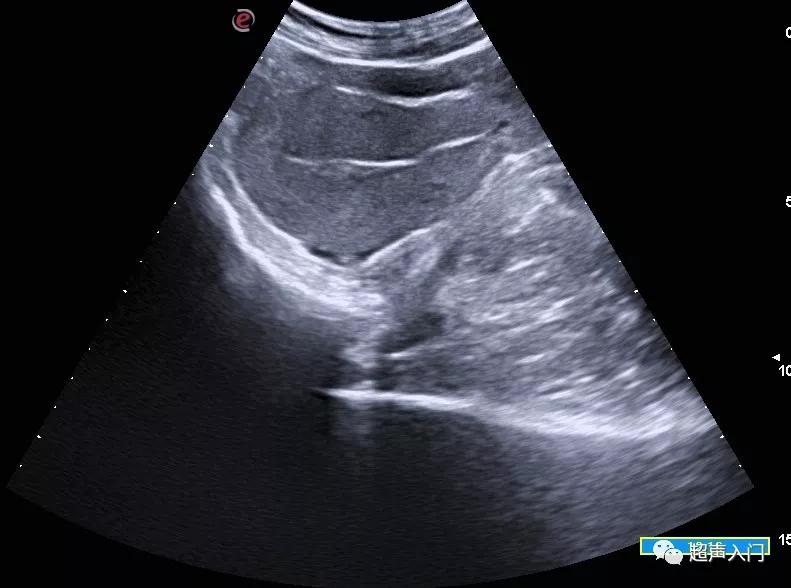

后倾后屈位: 纵切面宫体向后反屈,可见有折叠线,宫颈高于宫体,子宫体后壁紧靠子宫颈后壁。

后倾后屈位子宫(经腹纵切面)

后倾后屈位子宫(经阴道纵轴切面)